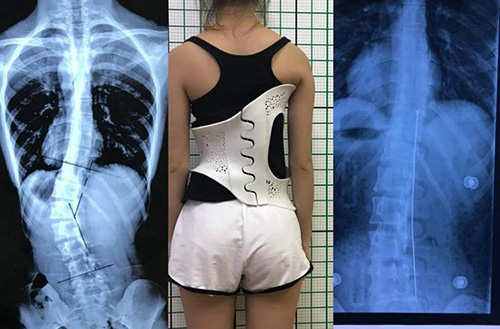

此外,在外固定支具研制方面,3D打印所起到的作用也不容忽視。對(duì)于意外摔傷導(dǎo)致骨折的患者來(lái)說(shuō),適宜的熱塑夾板、可卸式泡沫夾板、高分子夾板等外固定支具,有助于幫助患者快速恢復(fù),并降低發(fā)生二次骨折的風(fēng)險(xiǎn)。

(3D掃描和3D打印技術(shù)輔助制造的個(gè)性化脊柱矯正支具)